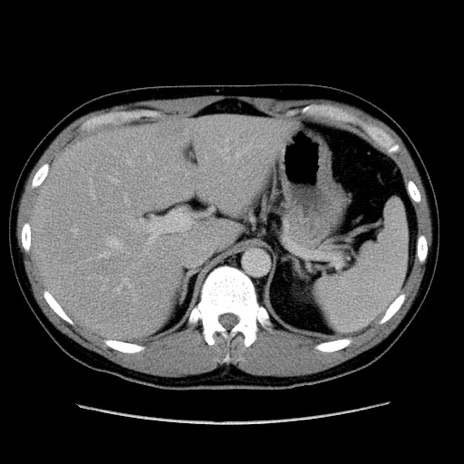

冠状断像

【症例】30歳代男性

【主訴】腹痛、嘔吐

【現病歴】昨晩から突然の腹痛あり、その後嘔吐、軟便も出現。腹痛が改善しないため救急搬送となる。2日前にしめ鯖の食事歴あり。

【身体所見】意識清明、苦悶様、BP 135/90mmHg、BT 35.7℃、腹部:平坦、やや硬、心窩部〜臍部に自発痛、圧痛あり、筋性防御+、反跳痛-

【データ】WBC 8100、CRP 0.57